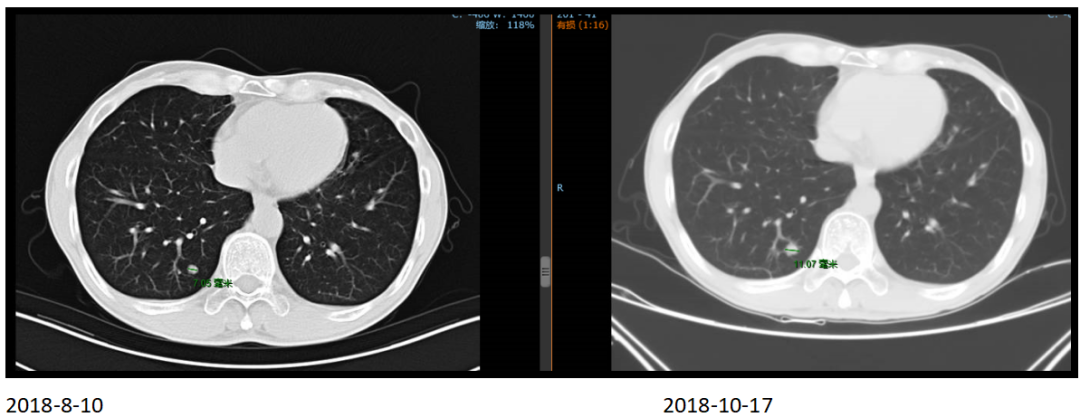

同时发现左颈部和肝脏多发转移灶。

2018年10月17日,化疗前

2019年1月24日,化疗后